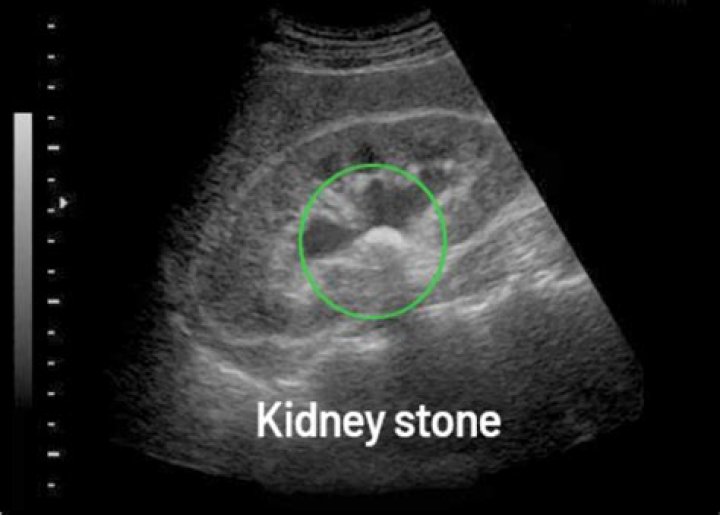

Score: 4.5/5 (25 votes) Pain associated with renal stone disease is typically caused by an obstructing stone that obstructs the flow of urine, which resu...